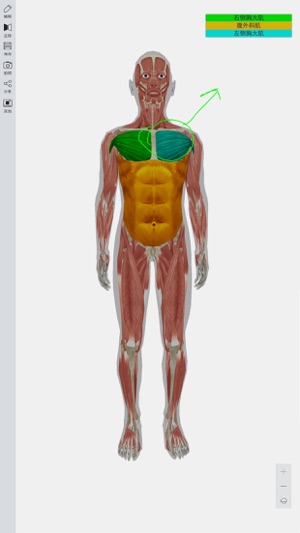

3D人体模型提供全三维数字人体模型,超过4000多个人体解剖结构,完整全面的解剖学数据,涵盖人体各个解剖系统,如神经,运动,呼吸,心血管,泌尿等系统,并配有文字注释,触发点等信息。

此APP功能强大,是广受欢迎的医学软件之一。其主要包括12个系统:

循环系统,消化系统,内分泌系统,皮肤系统,淋巴系统,肌肉系统,神经系统,生殖系统,泌尿系统,呼吸系统,骨骼系统和骨连接系统。

真正的3D特效,能360度任意角度查看,分层查看,进行相关组织或解剖结构隐藏,显示,完全再现人体解剖全过程。

能无限级的放大和缩小,远距离观察全景,近距离观察细节。